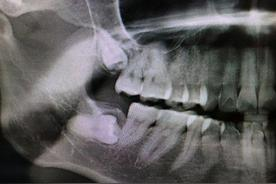

那為什么醫(yī)生會說她的智齒需要拔呢?一看片子,好家伙,這四顆牙齒雖說茁壯成長,但也確實(shí)是在各長各的,難怪醫(yī)生說要拔。

智齒阻生

如果只是長的不太整齊,但不影響其他牙齒,我們或許可以忍受,但我朋友有一顆盡頭牙是橫著長的,醫(yī)生說這叫阻生,阻生牙的力量很大,會推著其他牙齒往前擠,難怪她覺得讀書時候牙齒挺齊的,年紀(jì)越大牙齒卻越來越不整齊,那可能就是盡頭牙在“作怪”。

她的情況還比較嚴(yán)重,盡頭牙抵著前面一顆牙齒的牙根和牙冠,醫(yī)生告訴她,一天兩天沒感覺,但等到牙齒會疼的時候,問題就大了,到時候就兩顆牙都保不住。